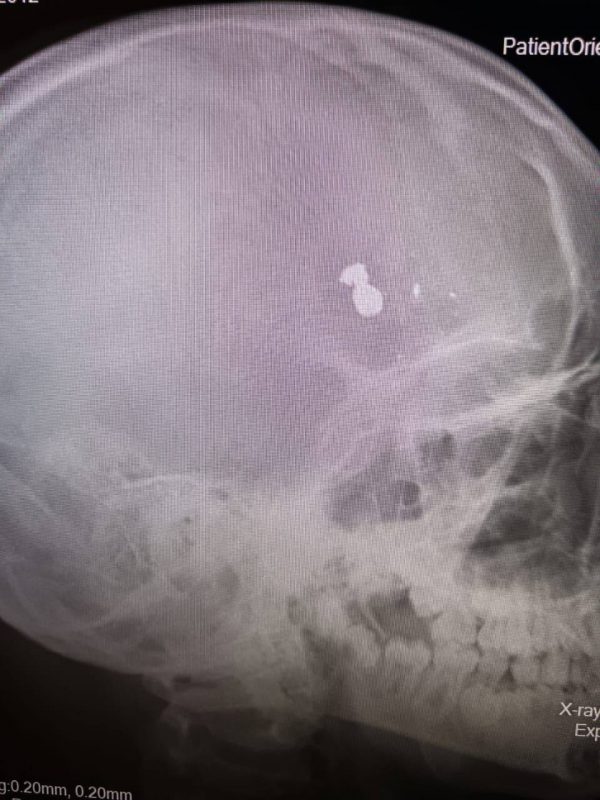

Как сообщается в telegram-канале регионального минздрава, пуля находилась в лобной доле черепа ребенка. После того, как фельдшеры перевезли мальчика в Саратов, бригада врачей приступила к срочной операции. Извлечение пули и осколков длилось пять часов.